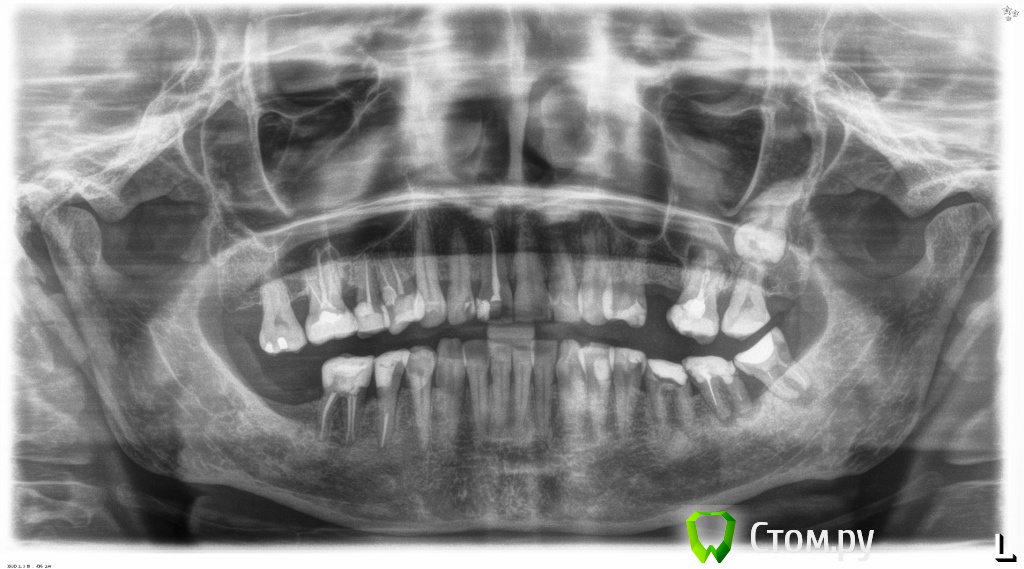

Dr.Sham Опубликовано 21 октября, 2014 Поделиться Опубликовано 21 октября, 2014 (изменено) Пациентка 55 лет с онкологией в прошлом.Аутоиммунный тиреоидит.Хочет красивые зубы, которыми можно жевать.Суставной компонент я не диагностирую, щелчков и посторонних шумов при открывании рта нет. Мышцы без гипертонуса, пальпаторно боли отмечает со стороны крыловидной медиальной и латеральной мышц слева.Фотки. Рентген. КТ пока не делал, хочется сделать с шаблоном, но пока с планом лечения не определились.Брекеты не хочет, каппы хочет, но я не знаю возможности лечения на каппах и доктора ответственного (С-Пб.) Фото: Модели в артикуляторе: ОПТГ Изменено 21 октября, 2014 пользователем Dr.Sham Ссылка на комментарий

dnsmc Опубликовано 21 октября, 2014 Поделиться Опубликовано 21 октября, 2014 Есть такая система элайнеры (прозрачные каппы), ими лечат скученность какая имеет место у пациентки, ну опять же нужно найти хорошего ортодонта.По мимо ортодонта, тут еще надо посетить и хирурга и терапевта(удалять лечить перелечить), если же вы не все сами делаете?!Нужно КТ, а потом уже точный план лечения составить.У меня вопрос, на модели нарисованы границы, это имеется ввиду поднять десну?Ну так на оптг видно что воспаление есть, зубы на удаление как мне кажется идут например 2.6 и 3.8 хотя на модели они есть. Интерестно, что будите делать дальше, жду плана лечения Ссылка на комментарий

togrul Опубликовано 21 октября, 2014 Поделиться Опубликовано 21 октября, 2014 Есть такая система элайнеры (прозрачные каппы), ими лечат скученность какая имеет место у пациентки, ну опять же нужно найти хорошего ортодонта.По мимо ортодонта, тут еще надо посетить и хирурга и терапевта(удалять лечить перелечить), если же вы не все сами делаете?!Нужно КТ, а потом уже точный план лечения составить.У меня вопрос, на модели нарисованы границы, это имеется ввиду поднять десну?Ну так на оптг видно что воспаление есть, зубы на удаление как мне кажется идут например 2.6 и 3.8 хотя на модели они есть. Интерестно, что будите делать дальше, жду плана лечения26 можно перелечить , а вот 3.8 удалять однозначно Ссылка на комментарий

Slaggy Опубликовано 21 октября, 2014 Поделиться Опубликовано 21 октября, 2014 (изменено) Суставной компонент я не диагностирую, щелчков и посторонних шумов при открывании рта нет. Мышцы без гипертонуса, пальпаторно боли отмечает со стороны крыловидной медиальной и латеральной мышц слева. "На глазок" - слева уровень ВЧ вырезки выше на 1 мм, значит сустав компенсирует этот мм. Вот вам и боли при пальпации.Если планируете тотал, сделайте МРТ суставов или аксиографию. Подстрахуйтесь.Возможно там хроника без обострений (сустав). А если по оптг смотреть (хоть это неверно "в корне") уровень носового хода, пазухи, альвеолярного отростка слева так-же выше на 1-2 мм - скорее всего в суставе найдете патологию, как минимум слева. Изменено 21 октября, 2014 пользователем Slaggy Ссылка на комментарий

Dr.Sham Опубликовано 22 октября, 2014 Автор Поделиться Опубликовано 22 октября, 2014 (изменено) Что Вы гадаете всё время? Вы померяли недостаток места во фронтальном отделе н/ч? Сможете Вы его компенсировать сепарацией? Если да, то нет разницы чем ровнять. Сделать интрузию боковых зубов позволит их пародонт? Вы продонтальный зонд брали в руки, а то об этом нет ни слова? Вы можете уже сказать какие зубы удалите, а какие останутся? Вот когда дадите ответы на эти вопросы, можно будет пойти дальше.Я не очень понимаю, как измерить недостаток места во фронтальном отделе нижней челюсти. Про интрузию тоже не знаю, каковы показания/противопоказания для этой манипуляции. Это должны решить пародонтолог и ортодонт? К сожалению, их в клинике нет. Если бы я сам знал все ответы на эти вопросы, то, наверное, и не постил бы эту тему здесь. а постил бы до и после. По теме: 36, 37 удалены, 38 - кандидат, 16 с трещиной тоже под удаление, 26 - с учетом всех проблем так же на выход. Остаются две верхние семерки - сильно выдвинутые. Вот я и спрашиваю, есть ли смысл их вколачивать? 46 с неадекватной непрямой реставрацией, думаю, под реставрацией безферрульный зуб будет. Так что, предполагаю, что в боковых отделах зубы будут удалены. Изменено 22 октября, 2014 пользователем Dr.Sham Ссылка на комментарий

Дмитрий Никитюк Опубликовано 22 октября, 2014 Поделиться Опубликовано 22 октября, 2014 Я не очень понимаю, как измерить недостаток места во фронтальном отделе нижней челюсти. Штангенциркулем.Всё просто на самом деле. Нужно измерять мезио-дистальные размеры резцов, просуммировать их и сравнить с имеющимся расстоянием между клыками (проволочку по форме зубного ряда изгибаете, а потом выпрямляете и к линейке). Про интрузию тоже не знаю, каковы показания/противопоказания для этой манипуляции. Зависит от состояния пародонта. Опора нужна (МИ) + время. По теме: 36, 37 удалены, 38 - кандидат, 16 с трещиной тоже под удаление, 26 - с учетом всех проблем так же на выход. Остаются две верхние семерки - сильно выдвинутые. Вот я и спрашиваю, есть ли смысл их вколачивать? 46 с неадекватной непрямой реставрацией, думаю, под реставрацией безферрульный зуб будет. Так что, предполагаю, что в боковых отделах зубы будут удалены. 38 на удаление.17 возможно ортодонт с пародонтологом дадут добро, но 27 в 28 точно не затолкаете. 46 под вопросом. У меня в практике есть понятие "диагностическое лечение" с целью определения прогноза. Определяем эндопрогноз (прицельный снимок + работа с СКК под микроскопом), пародонтологический прогноз (снимки + зондирование), ортопедический прогноз ( наличие феррула или возможность его создания). Пациент, который дает добро на это, прекрасно понимает, что я могу ему снять старую реставрацию и либо сохранить зуб, либо тут же его удалить (т.е. готов к худшему, но надеется). Естественно пациент платит деньги за это + за лечение или удаление. Ссылка на комментарий

Dr.Sham Опубликовано 22 октября, 2014 Автор Поделиться Опубликовано 22 октября, 2014 ШтангенциркулемНаверное, я и по фото на компе могу это сделать. И каким будет мой вывод? Получил я какие-то числа и что с ними делать?С 46 все понятно, спасибо, тоже есть диагностика под скопом.27 убивать и делать коронку, а десна и бифуркация? Значит в топку?17 если ортодонт не возьмется или зуб не "пойдет"? тоже убивать и короновать или в топку? В сухом остатке: снизу в боковых отделах все удалили, сверху, похоже, тоже. Далее хирургия в объеме-пародонтологическое пособие-установка винтов и возможная аугментауция (оценим по КТ), -удаление старых реставраций и устранение рецессий сверху и снизу Ортодонт посмотрит и скажет, что на счет фронта, я так понимаюДалее воск, мок ап, времяхи? Ссылка на комментарий